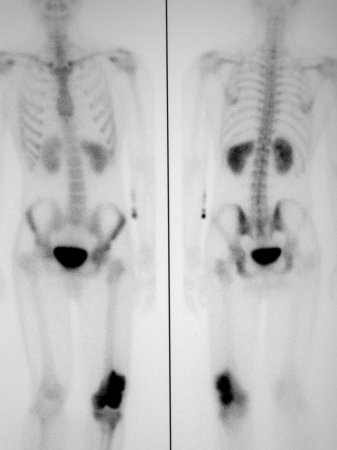

Usually uses technetium-99. Forms part of the secondary staging. Will reveal approximate extent of primary lesion and highlight any skip or distant metastases.[Figure caption and citation for the preceding image starts]: Bone scan; high radionuclide uptake at tumour sitePersonal collections of Dr Michael J. Klein and Dr Luminita Rezeanu [Citation ends].

Result

intensely hot signal at primary tumour site; may also identify skip or distant metastases